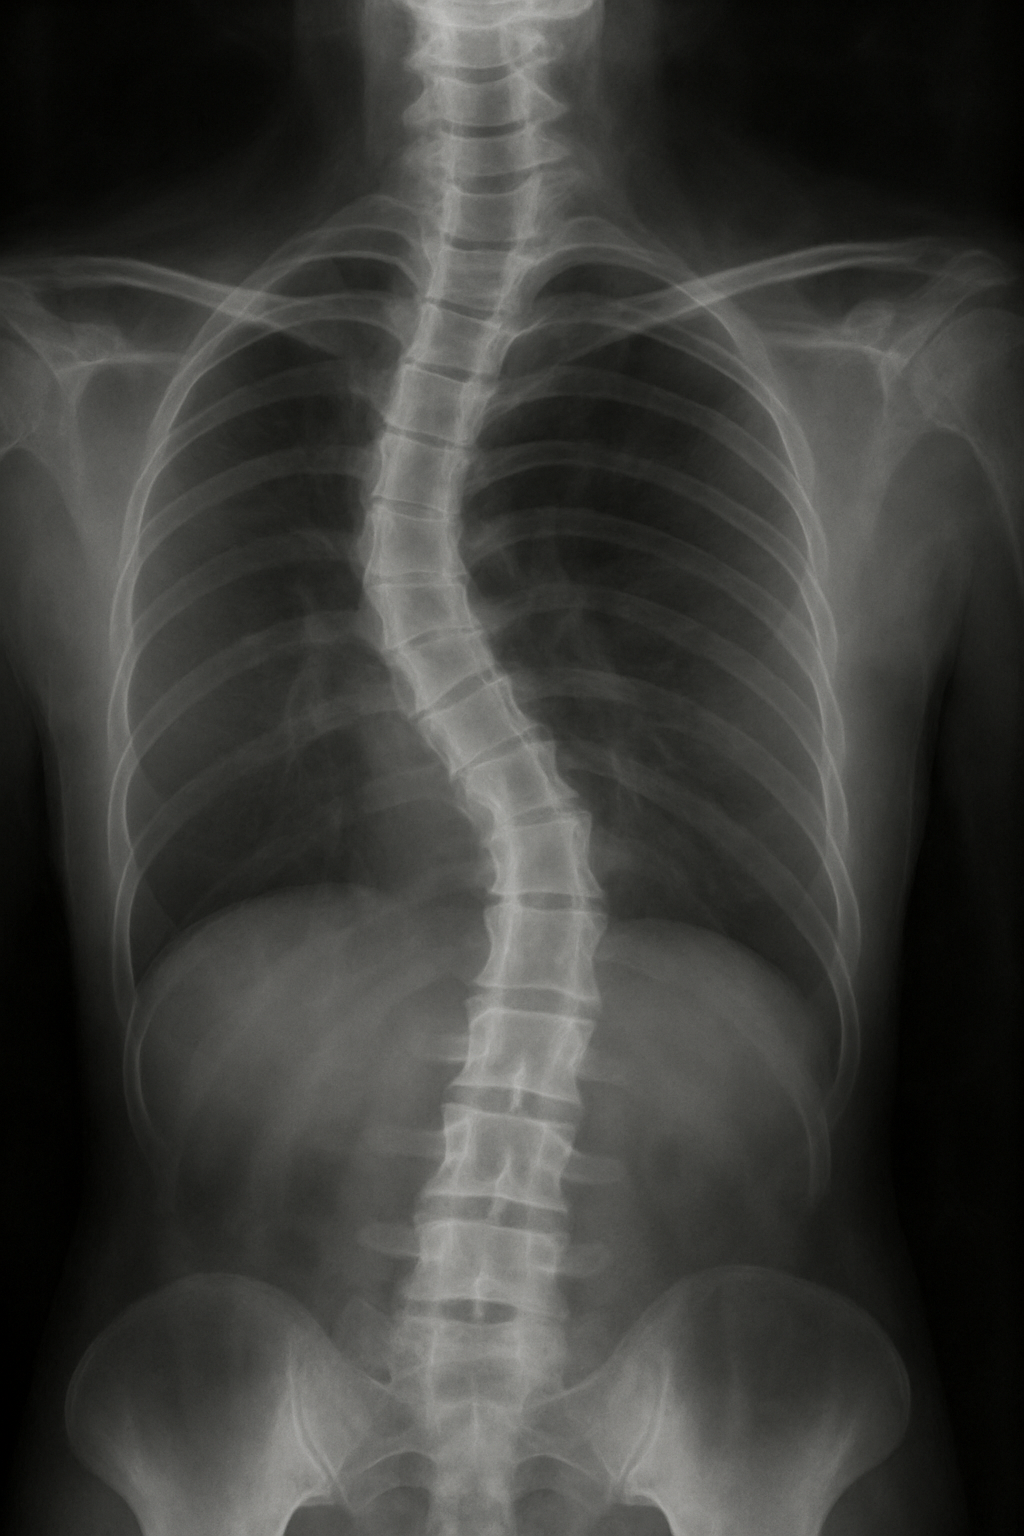

La propuesta se estructura en cuerpos de trabajo articulados visual y discursivamente, abordando temas como la disociación, el pensamiento retorcido, la hegemonía corporal y la estética clínica. Es una obra que se pregunta: ¿Qué es lo normal? ¿Qué es lo torcido o lo que se quiere enderezar? ¿Dónde termina lo bello y empieza la herida?